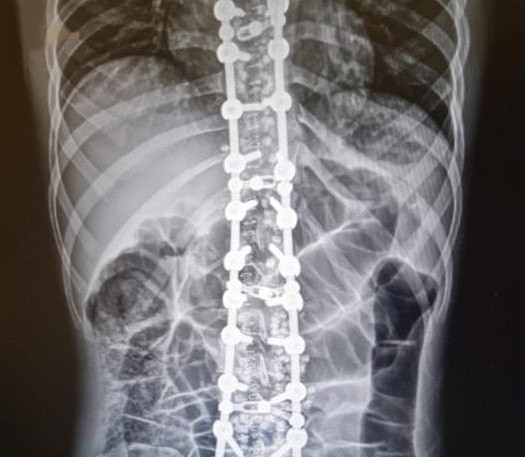

Ordu'nun Fatsa ilçesinde 17 yaşındaki B.Ç., yaklaşık 10 yıldır omurgasındaki eğilmeden şikayeti nedeniyle Fatsa Devlet Hastanesine başvurdu. Gerekli tetkikleri yapılan hasta, Ortopedi ve Travmatoloji Uzmanı Opr. Dr. Mehmet Onur Sarıhan tarafından ameliyat edildi. Sağlığına kavuşan hasta taburcu edildi.

Skolyoz rahatsızlığı ve yapılan ameliyatla ilgili bilgi veren Opr. Dr. Mehmet Onur Sarıhan, "Skolyoz omurganın yana 10 derecenin üzerindeki eğilmedir. Normal ve sağlıklı omurgada, omurlar arkadan bakıldığında yukarıdan aşağıya yani boyun, sırt ve bel bölgelerinde düz bir hat şeklinde uzanır. Skolyoz da ise omurlar sağa veya sola doğru yer değiştirir ve aynı zamanda kendi eksenleri etrafında döner. Bu nedenle üç boyutlu bir deformite (şekil bozukluğu) olarak tanımlanır. Skolyoza bağlı olarak omurga dışında kalça, göğüs kafesi ve kürek kemiklerinde de kaymalar oluşur, duruş ve görüntü bozukluğu ortaya çıkar. Gelişme çağındaki çocuklarda bu durum, gelişen ve büyüyen omurgada anormal yüklenmeye ve bunun sonucu olarak da omurlarda deformelere neden olur" dedi.

Skolyoz (omurga eğriliği) ve omurgada dar kanal cerrahisi ameliyatlarının Fatsa'da başarılı bir şekilde yapıldığını söyleyen Opr. Dr. Mehmet Onur Sarıhan, "Genç yaşlarda tespit edildiğinde tedavide başarı oranı ciddi olarak artmaktadır. Bu tür rahatsızlığı olanlar artık ilçemizde başarılı bir şekilde tedavilerini olabilecekler" diye konuştu.